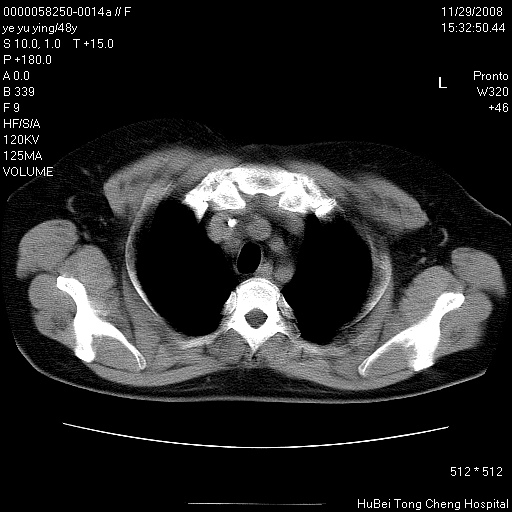

以下是引用zsl6918在2008-11-29 21:47:00的发言:[br]恶性肿瘤病史,转移瘤首先考虑。脂肪肝,胆囊结石。

以下是引用liuyue在2008-11-30 5:44:00的发言:[br]1.左肺病变,首先考虑感染性病变,转移待排;建议治疗后复查。[br]2.肝脏密度普遍减低,考虑与化疗有关。[br]3.胆囊结石.